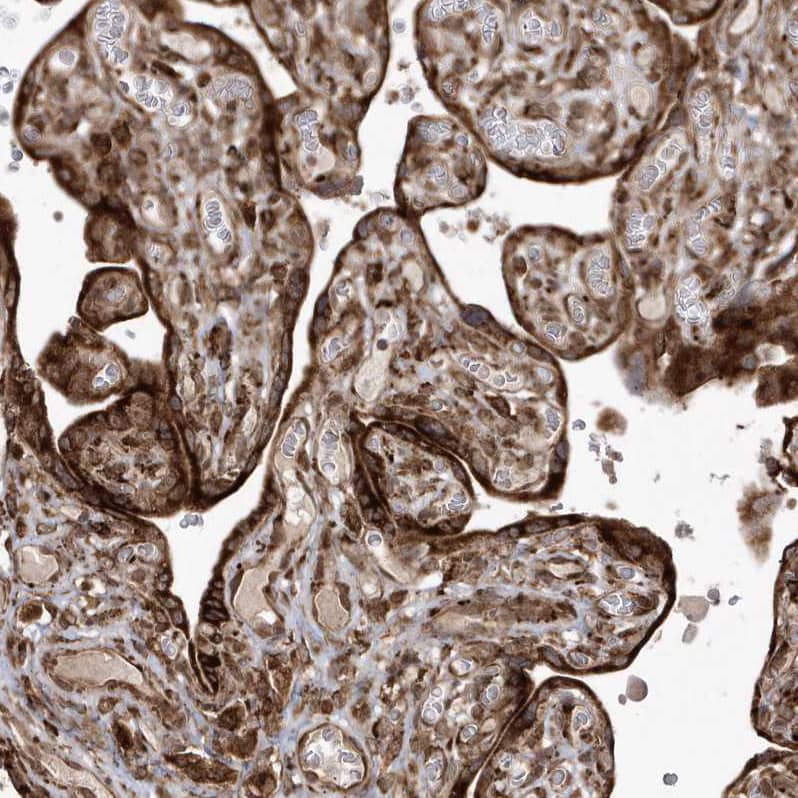

Staining of human placenta shows strong cytoplasmic positivity in trophoblastic cells.